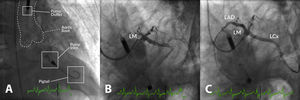

DeviceDevice implantation was performed by an experienced interventional cardiologist under fluoroscopic guidance in the catheterization laboratory (Figure 1). The femoral route was used in all cases. PCI was performed according to the center's standard practice and the need for prophylactic pVAD in the setting of HR-PCI was based on the clinical judgment of the operator and overall risk assessment.

Example of high-risk percutaneous coronary intervention (PCI) supported with an Impella® CP in a patient with multivessel disease presenting with acute myocardial infarction, severe left ventricular (LV) dysfunction and shock. (A) Impella® CP device placed in the LV cavity and ascending aorta; the main radiographic components are depicted; (B) coronary angiogram showing occlusion of the proximal left anterior descending (LAD) and mid-left circumflex (LCx) coronary arteries; (C) coronary angiogram following PCI of the LAD and LCx. LM: left main coronary artery.